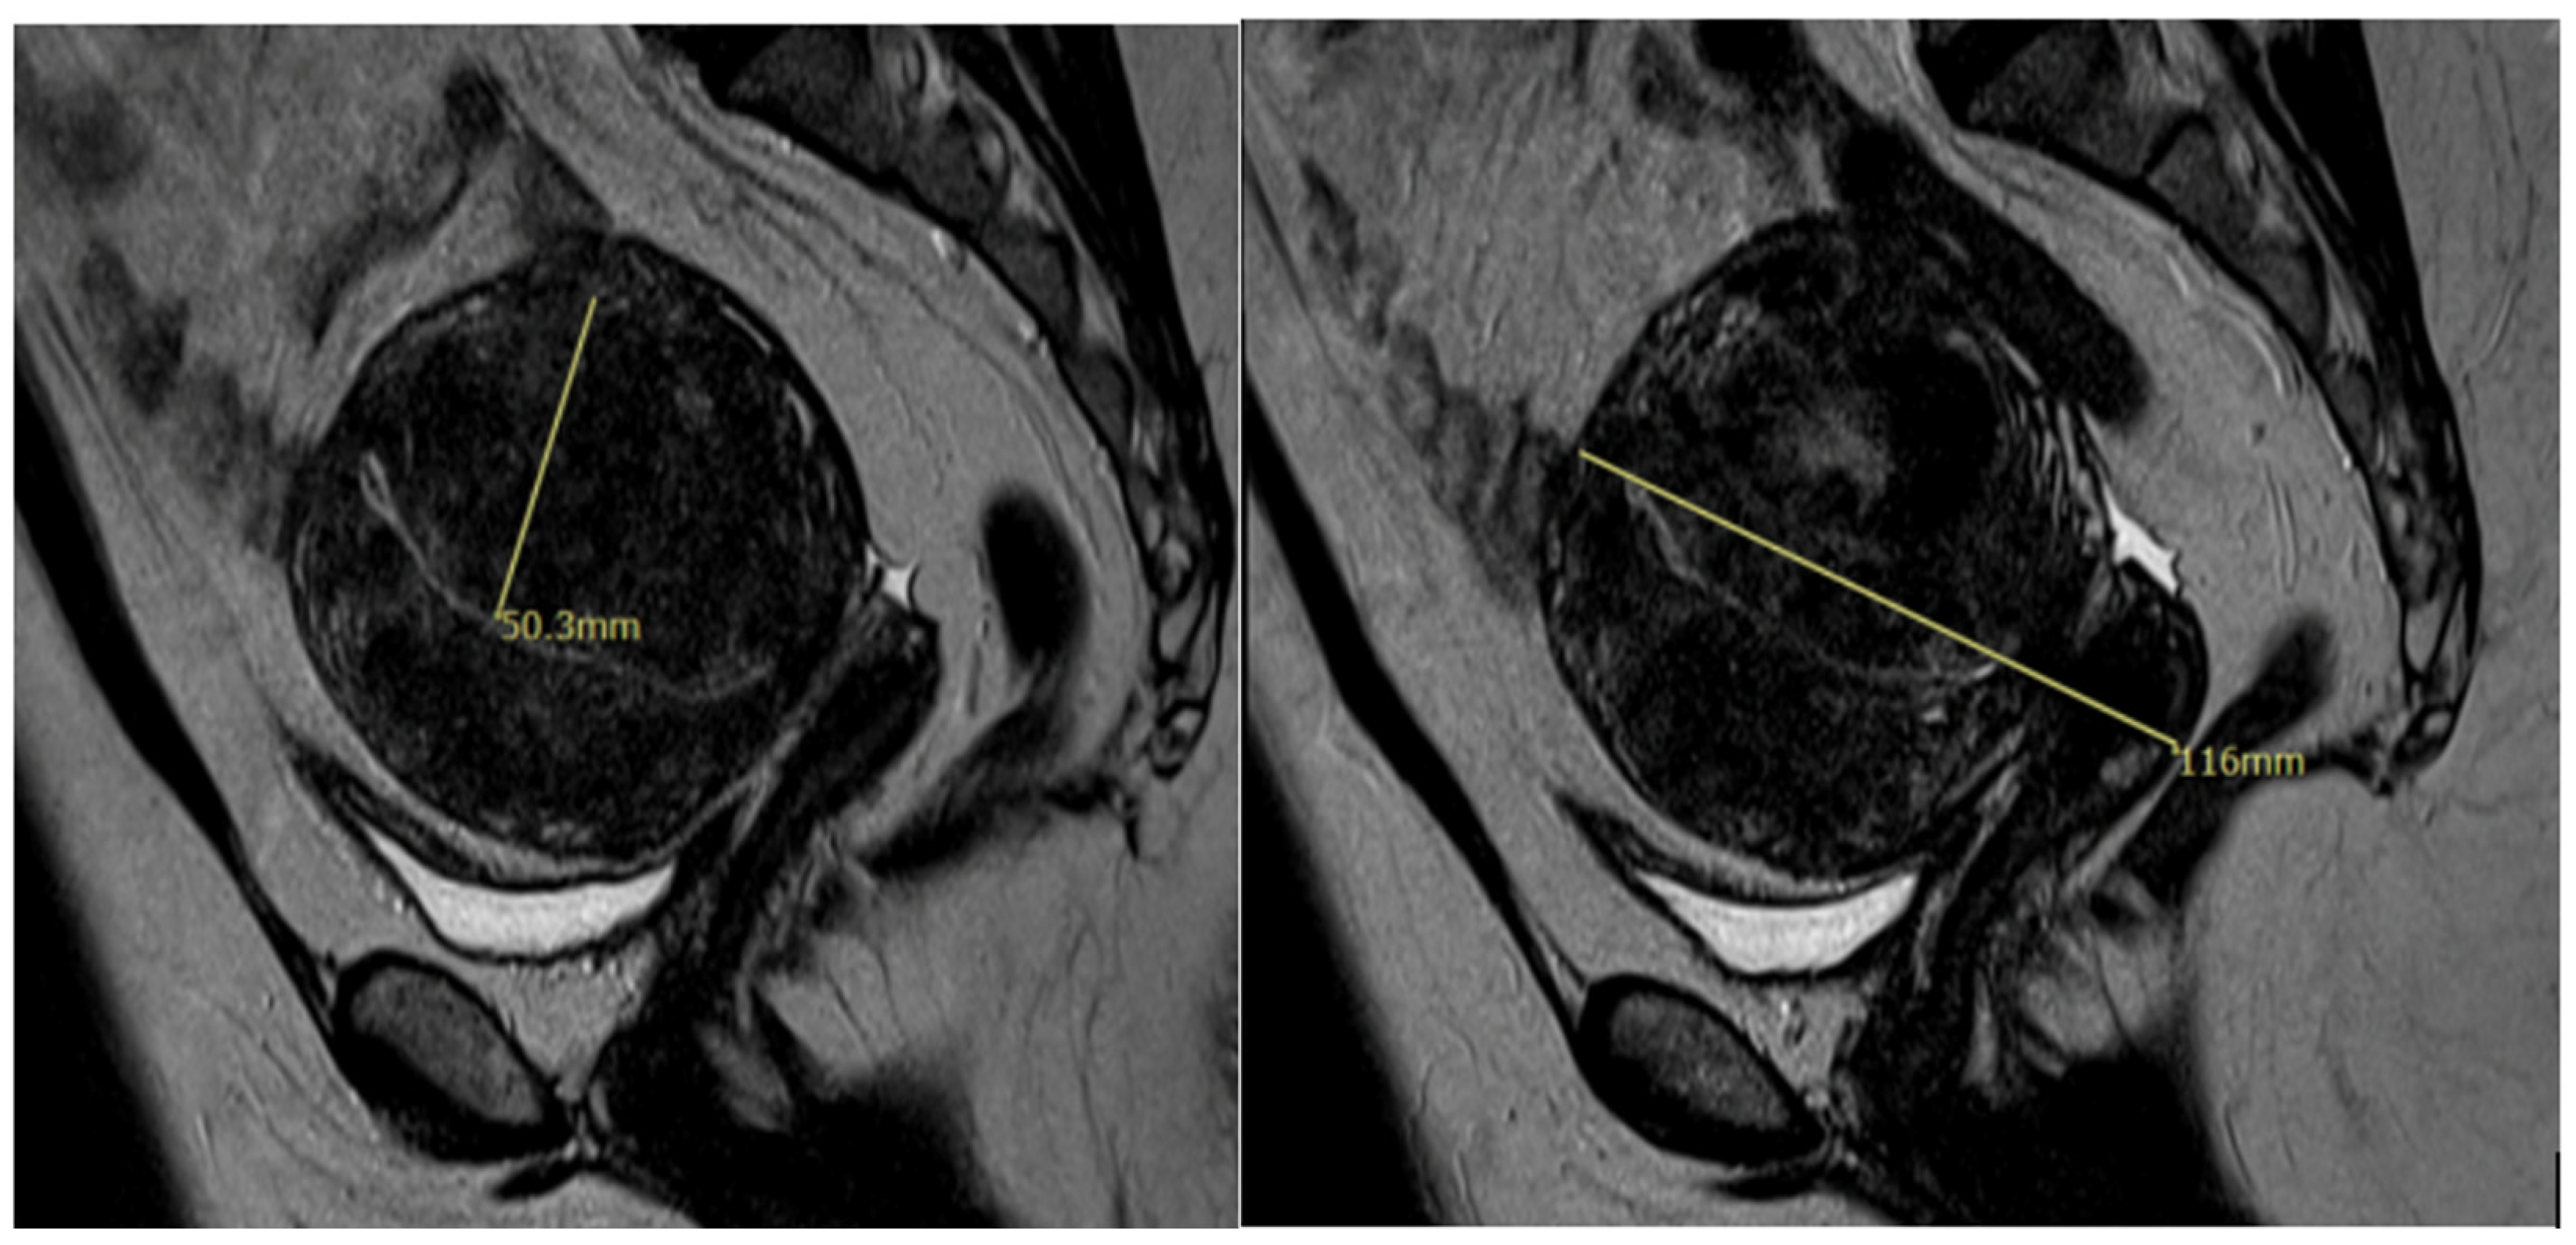

- Zhang, W.; Pan, N.; Han, B.; Li, X.; Li, R.; Ma, C.; Qiao, J. Association Between Uterine Volume and In Vitro Fertilization (IVF) Reproductive Outcomes of Infertile Patients with Adenomyosis. Reprod. Sci. 2023, 30, 3123–3131. [Google Scholar] [CrossRef] [PubMed]